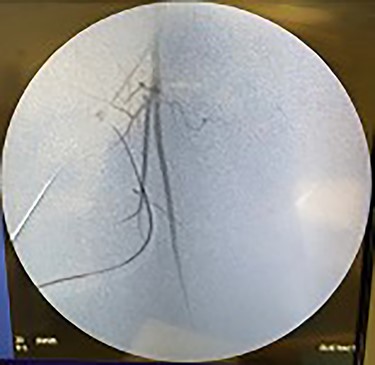

Catheter arteriogram results showed significant occlusion of the left iliac artery (Figs 3 and 4), the right iliac artery (Fig. 1), as well as the distal abdominal aorta (Fig. 2). There were numerous collateral vessels noted, indicating the presence of long-standing proximal stenosis (Fig. 1). The decision was made to use angioplasty to help widen the areas of stenosis. An 8 mm × 40 mm Passeo balloon was advanced from the right femoral artery into the left iliac artery (Fig. 7) and insufflated to 6 mmHg (Fig. 6). The balloon was allowed to remain expanded for 1 min and then was deflated. Next, the distal aorta was repaired in a similar fashion. The balloon was advanced into the distal aorta from the right femoral access and insufflated to 12 mmHg (Fig. 8). The balloon was allowed to remain expanded for 90 s.

Fluoroscopy of right iliac artery showing vast collateral vascular formation, indicating long-standing proximal obstruction.